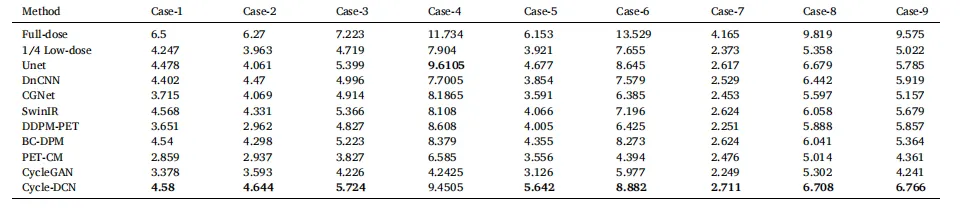

The proposed Cycle-DCN model was systematically compared with several established image denoising and restoration methods, including widely used U-Net, classic denoising model DnCNN (Zhang et al., 2017), the more recent image restoration model CGNet (Ghasemabadi et al., 2024), the Swin Transformer-based SwinIR, CycleGAN, and three diffusion-based approaches: DDPM-PET, PET-CM, and BC-DPM. Table 1provides the quantitative results, showing the mean, standard deviation, and statistical significance based on paired t-tests for each evaluation metric. Fig. 4(a) presents a visual comparison of a representative slice across the nine models, along with the corresponding full-dose and low-dose images at three different dose levels.For ¼ low-dose images, the PSNR, SSIM, and NRMSE metrics are comparable across all evaluated models. While DnCNN and SwinIR slightly outperforms Cycle-DCN in some measures, these differences are not statistically significant (p > 0.05). In contrast, for the more challenging 1/24 low-dose images, Cycle-DCN achieves superior metric values. The three diffusion-based methods—DDPM-PET, PET-CM, and BC-DPM—consistently yielded inferior performance under all the three low-dose conditions. As shown in Fig. 4(a), U-Net and DnCNN result in excessive smoothing, leading to increased deviation from the full-dose images at lower dose levels, with small sulci becoming nearly indistinguishable. However, Cycle-DCN remains closer to the full-dose images, demonstrating better robustness. In the enlarged views in Fig. 4(b), Cycle-DCN uniquely preserves brain structures such as sulci and gyri, producing visual outputs more consistent with full-dose images compared to other models. Among the three diffusion-based methods, DDPM-PET produced visually promising results across all dose levels. However, the performance of BC-DPM (trained unconditionally) and PET-CM (with two-step sampling) deteriorated rapidly as the dose decreased, resulting in significantly degraded image quality.

4.1 定量评估 4.1.1 峰值信噪比(PSNR)、结构相似性指数(SSIM)及归一化均方根误差(NRMSE)对比 将所提Cycle-DCN模型与多种已有的图像去噪和恢复方法进行了系统对比,包括广泛使用的U-Net、经典去噪模型DnCNN(Zhang等,2017)、较新的图像恢复模型CGNet(Ghasemabadi等,2024)、基于Swin Transformer的SwinIR、CycleGAN,以及三种基于扩散的方法(DDPM-PET、PET-CM和BC-DPM)。表1给出了定量结果,包括各评估指标的均值、标准差以及基于配对t检验的统计显著性。图4(a)展示了九种模型在三个不同剂量水平下,代表性切片的视觉对比,同时呈现了对应的全剂量和低剂量图像。 对于¼低剂量图像,所有评估模型的PSNR、SSIM和NRMSE指标表现相当。尽管DnCNN和SwinIR在部分指标上略优于Cycle-DCN,但这些差异无统计学意义(p > 0.05)。相比之下,在更具挑战性的1/24低剂量图像中,Cycle-DCN取得了更优的指标值。三种基于扩散的方法(DDPM-PET、PET-CM和BC-DPM)在所有三个低剂量条件下均表现出持续劣势。如图4(a)所示,U-Net和DnCNN存在过度平滑问题,导致在低剂量水平下与全剂量图像的偏差增大,细小脑沟几乎无法区分。而Cycle-DCN始终更接近全剂量图像,展现出更强的鲁棒性。在图4(b)的放大视图中,Cycle-DCN独特地保留了脑沟、脑回等脑部结构,生成的视觉结果比其他模型更接近全剂量图像。在三种基于扩散的方法中,DDPM-PET在所有剂量水平下均产生了视觉上较理想的结果,但无监督训练的BC-DPM和两步采样的PET-CM的性能随剂量降低迅速下降,导致图像质量显著退化。

Table 2 Comparison of CNR across 9 Cases for Different Models

表2 不同模型在9个病例中的对比噪声比(CNR)对比